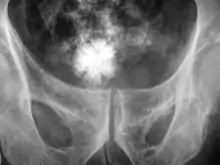

Diagnosis

The diagnosis of bladder stone includes urinalysis, ultrasonography, x rays or cystoscopy (inserting a small thin camera into the urethra and viewing the bladder). The intravenous pyelogram can also be used to assess the presence of kidney stones. This test involves injecting a radiocontrast agent which is passed into the urinary system. X-ray images are then obtained every few minutes to determine if there is any obstruction to the contrast as it is excreted into the bladder. Today, intravenous pyelogram has been replaced at many health centers by CT scans. CT scans are more sensitive and can identify very small stones not seen by other tests.[8]

Jackstone calculus

Jackstone calculi are rare bladder stones that have an appearance resembling toy jacks. They are almost always composed of calcium oxalate dihydrate and consist of a dense central core and radiating spicules. They are typically light brown with dark patches and are usually formed in the urinary bladder and rarely in the upper urinary tract. Their appearance on plain radiographs and computed tomography in human patients is usually easily recognizable. Jackstones often must be removed via cystolithotomy.[10]